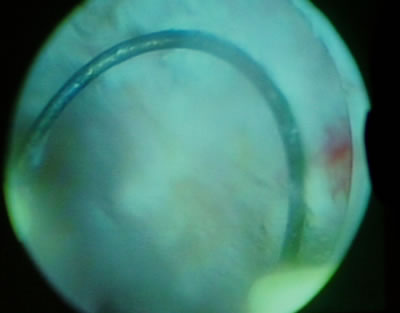

Этапы резекции доброкачественной гиперплазии предстательной

железы.